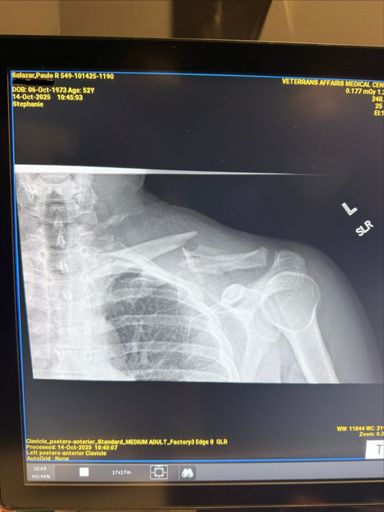

Ranger down! Collar bone is broken. Going to the ER. Cycling season is over for me this year.